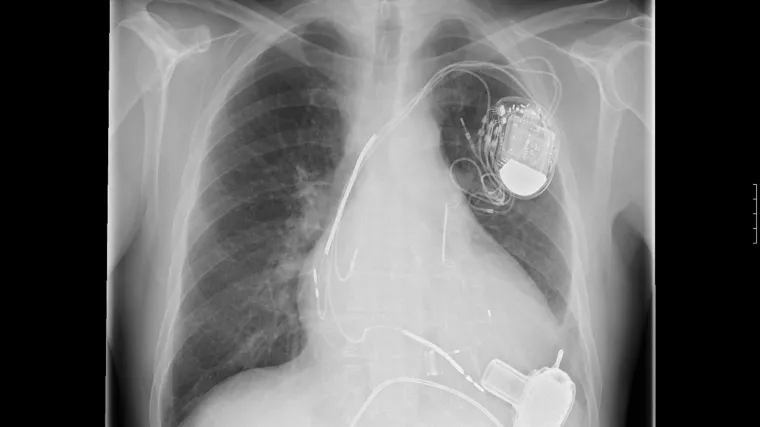

Izumili jestivu bateriju koja pokreće medicinske uređaje u tijelu

Probavljivi medicinski uređaji nude te i brojne druge primjene, ali glavni izazov je kako učiniti njihov izvor energije sigurnim za naša tijela.